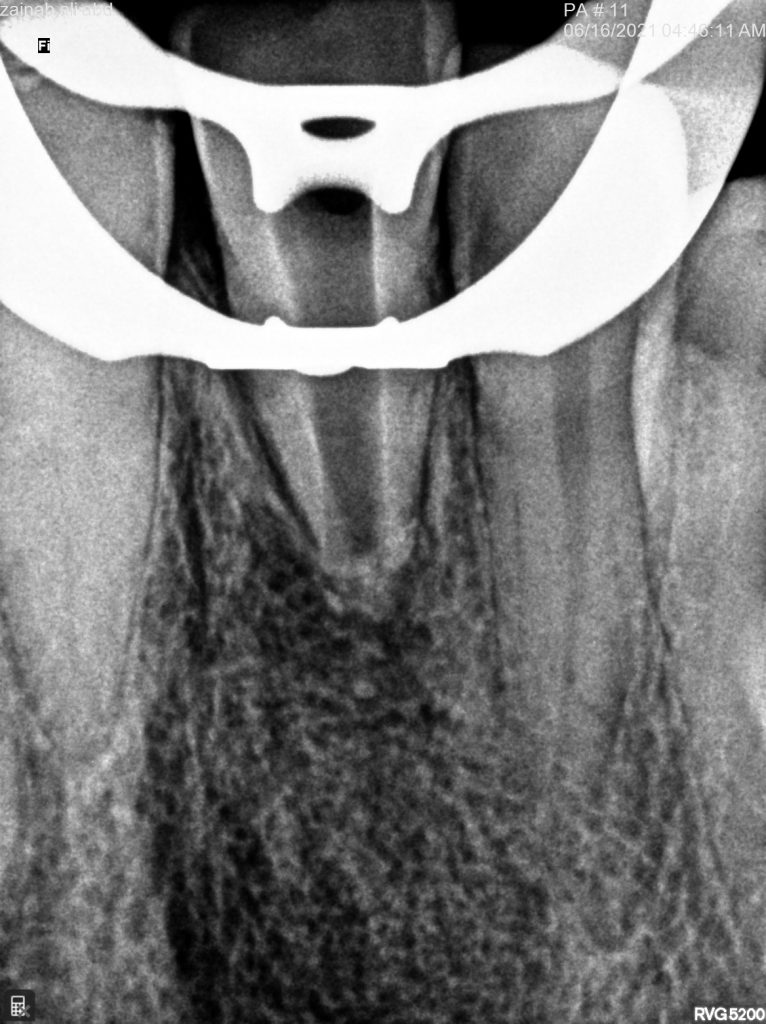

in the first visit access opening and thorough irrigation with sodium hypochloride till all the pus removed and application of non setting calcium hydroxide for one month

Discoloration of the affected tooth